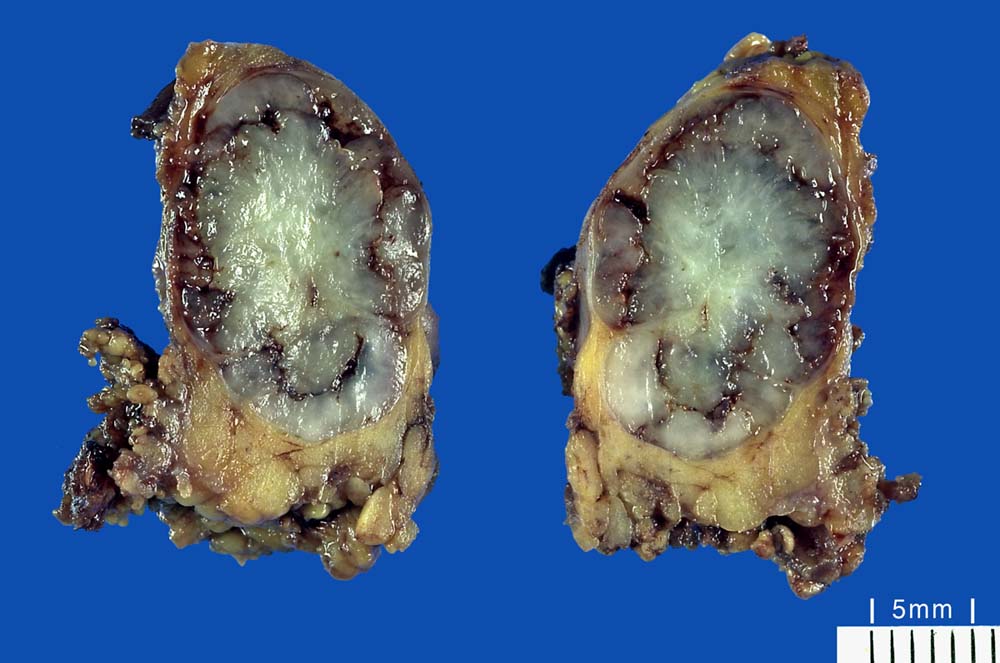

Makroskopie:

Makroskopisch sind pleomorphe Adenome scharf begrenzt. In den grossen Speicheldrüsen sind die meist solitär wachsenden Knoten von einer Kapsel umgeben, nicht aber in den kleinen Speicheldrüsen. Rezidivtumoren bilden oftmals multiple Knoten.

Beim Vorliegen von Satellitenherden kann der Pathologe nicht mit Sicherheit angeben, ob die Resektion im Gesunden erfolgte oder ob weitere Satellitenherde in situ verblieben sind.

Der Tumor sollte vollständig entfernt werden. Eine Tumorenukleation (Ausschälung aus der Kapsel) stellt eine ungenügende Therapie dar und führt in 20-45% zu Rezidiven (Rezidivrate bei Parotidektomie lediglich 2-3%).

Die oft multinodulären Rezidive können Jahre nach Erstdiagnose auftreten. Langbestehende pleomorphe Adenome bzw. deren Rezidive können zu Karzinomen entarten (Karzinom ex pleomorphes Adenom). Das Durchschnittsalter der Karzinompatienten liegt 13 Jahre höher als bei den Adenomen. Das Lebenszeitrisiko für die Entartung eines pleomorphen Adenoms beträgt 3 – 10‍%. Histologisch findet sich in diesen Fällen eine Mischung von pleomorphem Adenom und Adenokarzinom. Das Karzinom kann nicht invasiv (innerhalb der Tumorkapsel) oder invasiv wachsen. Erstere weisen bei vollständiger Exzision eine gute Prognose auf, letztere zeigen ein 5 Jahres-Überleben von 25-65%.